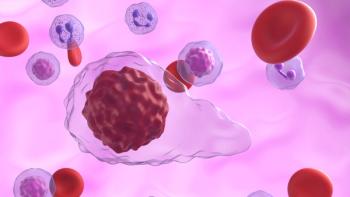

A 1-time dose of arlo-cel demonstrated safety and efficacy in patients with relapsed or refractory multiple myeloma that was previously treated.

Subcutaneous daratumumab is well tolerated, but ongoing immune monitoring is key to managing infection risk in patients with multiple myeloma.